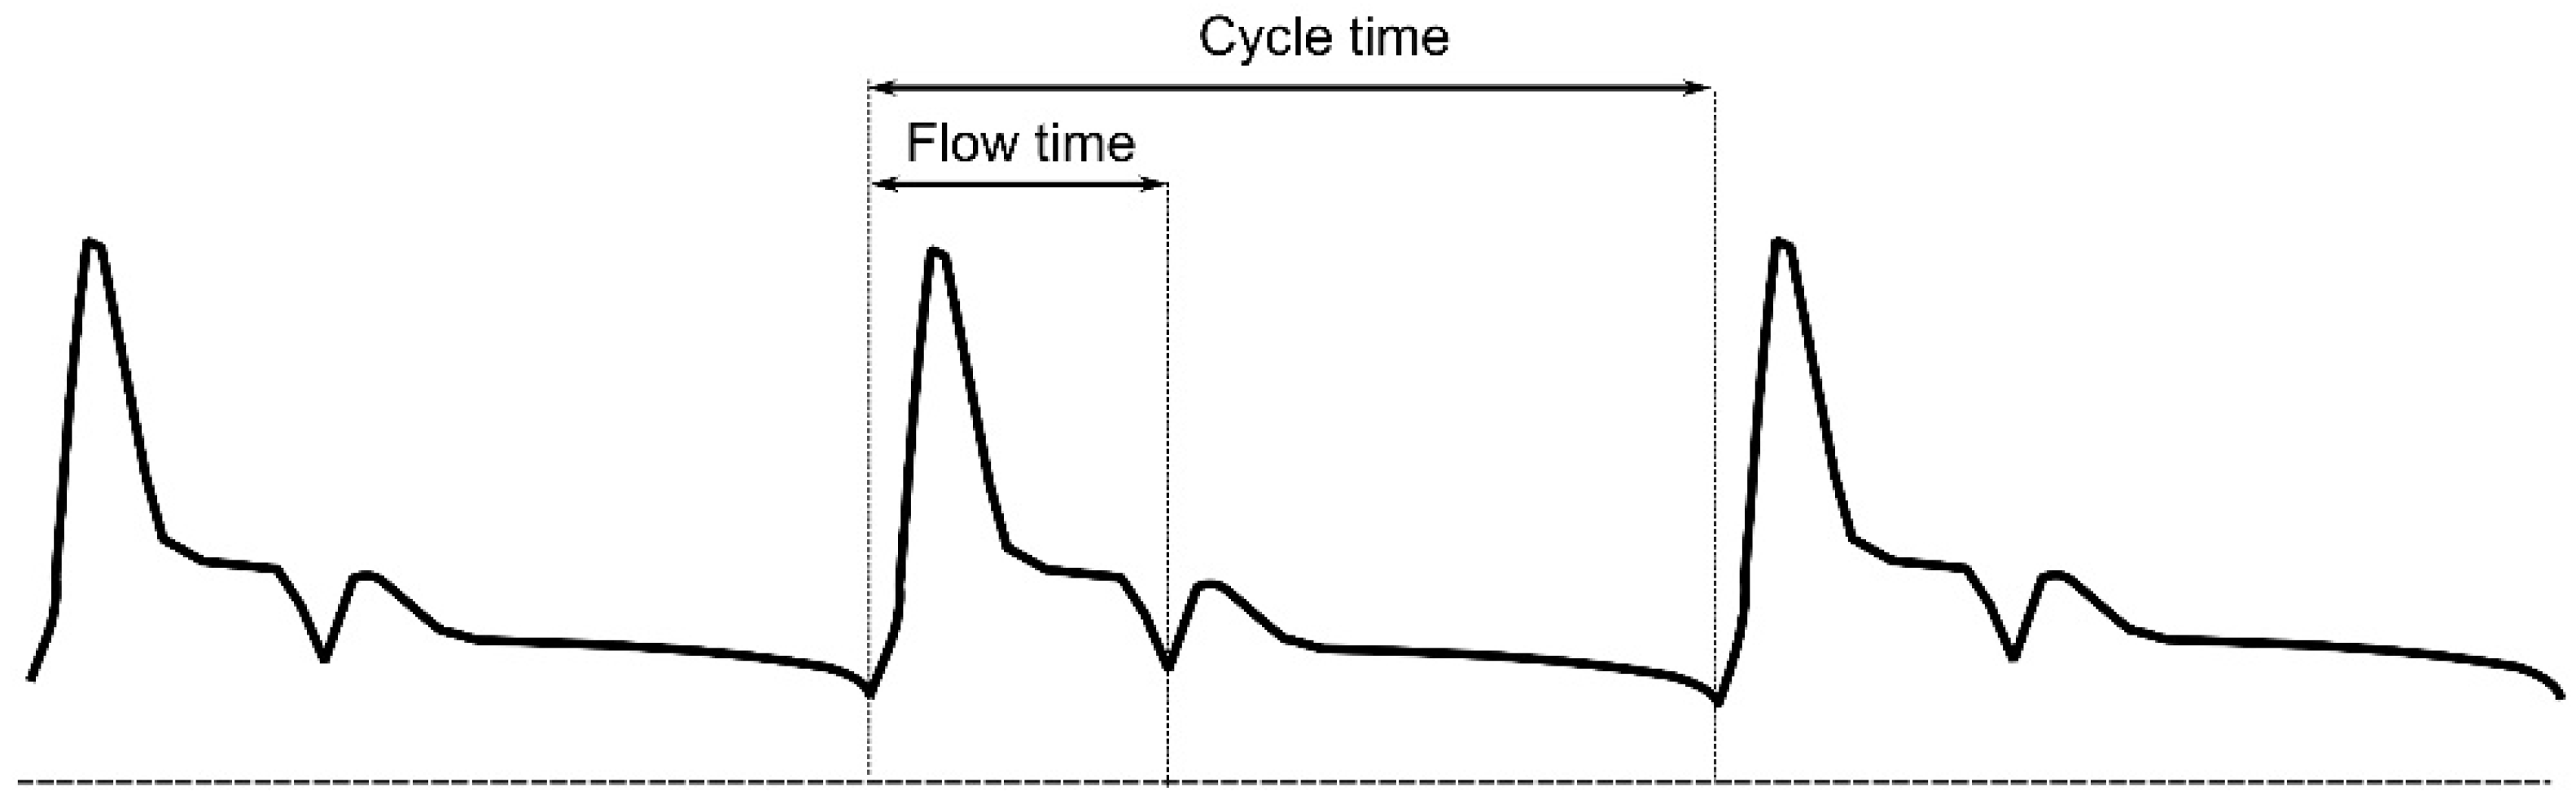

5. Hepatic Venous Flow